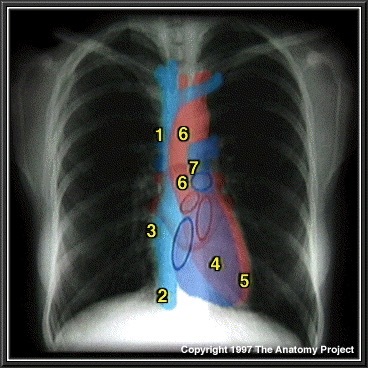

What structure is indicated by 1 on the figure below?

Superior Vena Cava

What structure is indicated by 2 on the figure below?

Inferior Vena Cava

What structure is indicated by 3 on the figure below?

Right atrium

What structure is indicated by 4 on the figure below?

Right ventricle

What structure is indicated by 5 on the figure below?

Left ventricle

What structure is indicated by 6 on the figure below?

Ascending Aorta and Aortic Arch

What structure is indicated by 7 on the figure below?

Pulmonary vasculature